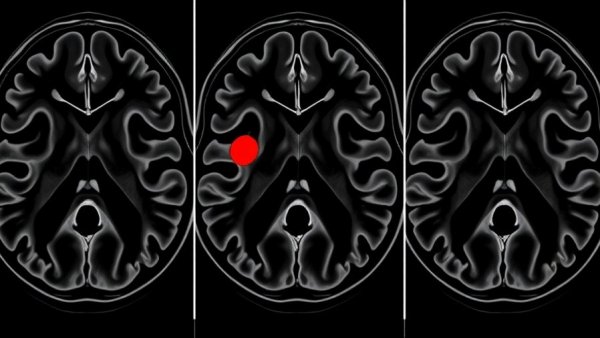

MRI in Active Surveillance for Prostate Cancer: detailed scans with highlighted regions.

The Search for Accuracy: MRI in Active Surveillance for Prostate Cancer

As advancements in medical imaging technologies continue to emerge, significant debates around their application in oncological practices persist. One such area of importance is the use of magnetic resonance imaging (MRI) in active surveillance for prostate cancer— a management strategy favored for men diagnosed with low-risk tumors. Recent research indicates that while prostate MRI is valuable, it is still not ready to entirely replace biopsies as a confirmatory step in active surveillance protocols.